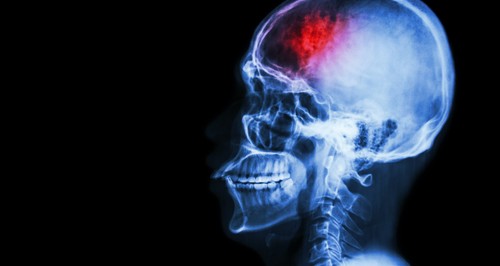

At least 1.5 million people suffer from a traumatic brain injury (TBI) each year. TBI can happen as focal injuries such as when a head hits a windshield. This direct impact can cause damage to the area of the brain where the initial contact occurred as well as causing the brain to slam against the skull in the opposite direction of the initial blow. Focal lesions in these areas can be seen on brain imaging in many cases.

Diagnosing TBI can be challenging when the injury is classified as mild. However, new imaging techniques are providing significant tools for physicians to not only diagnose the initial acute injury, but also to determine the full nature and extent of the injury and prognosis for that injury.